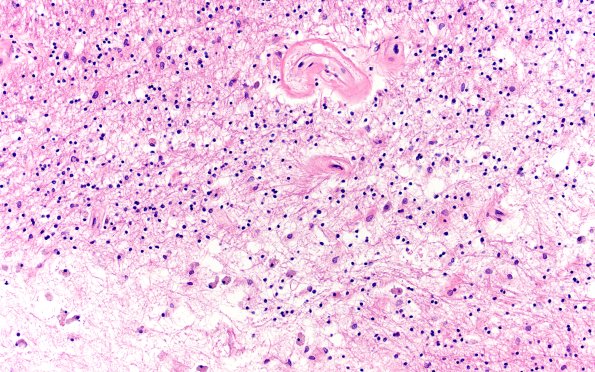

18E8,9 Higher magnification of image #18E7 showing acellular vessels, reactive astrocytosis, parenchymal loss and admixed macrophages. There are multifocal, 0.1 to 0.3 cm areas of granular dystrophic calcifications within the white matter with surrounding gliosis, axonal spheroids, and foamy macrophages (H&E)